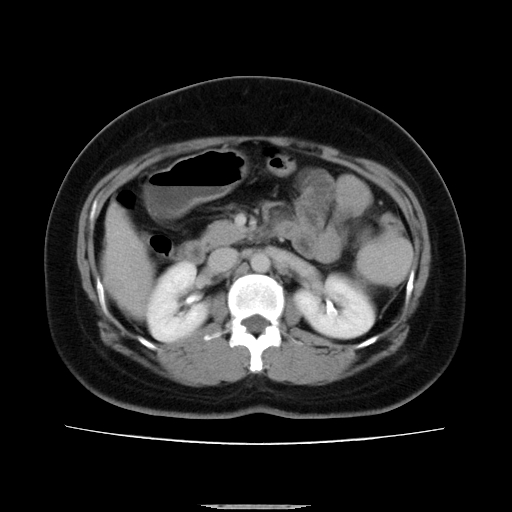

标题: CT14225:女性46岁。当地B超示肝内占位,来我院作CT检查。请 [打印本页]

标题: CT14225:女性46岁。当地B超示肝内占位,来我院作CT检查。请

速升速降,支持肝癌.脾体积增大,形态欠规整,请询问病史是否做过脾动脉栓塞.

肝内结节强化特点符合原发性肝癌表现,脾脏改变考虑为增大及先天发育所致。

肝内结节强化特点:快进快出符合原发性肝癌表现

肝内结节强化特点符合原发性肝癌表现。脾大。